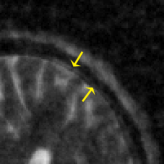

Refer to caption

Figure 2: Comparison between the conventional CS-MRI and the off-the-grid CS-MRI approach.

Generally, it is impossible to directly solve Eq. 3.5 without any further information. Nevertheless, by imposing the prior information of u𝑢u (in the continuous domain) into Eq. 3.5, we can exploit the continuous domain regularization, and reduce the basis mismatch; see Fig. 2 for the schematic comparison. For this purpose, we follow [51] and consider the following piecewise constant function model of the proton density u𝑢u: